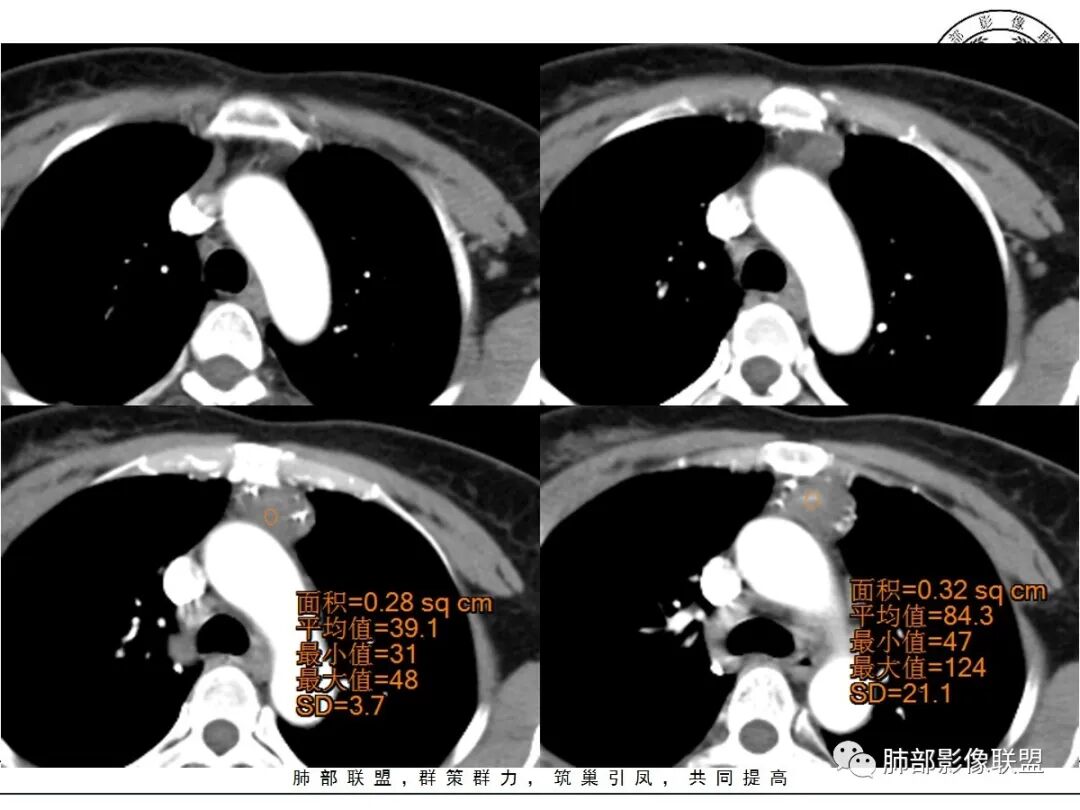

红星:女性病人48岁,前上纵隔,类圆形的实性病变,平扫密度比较均匀,周围卷见点状的钙化灶,增强扫描明显的强化, 多时相扫描中心可见跟大血管强化幅度一致的结节灶。常规胸腺瘤?鉴别血管瘤?

春秋:48岁,女性,前纵膈软组织肿物,有分叶,边缘毛糙,周边多发点状钙化,强化可见明显强化区,考虑血管瘤,鉴别胸腺癌。

周太狼:中年女性,前纵隔肿块,边界清,内不规则钙化灶,增强中央明显强化,与邻近血管强化程度相似。纵隔内无明显增大淋巴结。考虑良性或低度恶性病变。疾病谱:CD、副节、血管瘤、胸腺瘤/癌。个人倾向于CD或血管瘤可能大一些。

三个石头:前纵隔占位,残余胸腺组织可见,边缘钙化,增强中央出现与血管同步强化结节,病灶延迟强化。脉管瘤?胸腺瘤?血管瘤?异位甲状腺?

不吝慷慨:前上纵隔,边缘钙化,中央强化非常明显,形态不考虑胸内甲状腺,胸腺瘤强化又太明显,考虑嗜铬肿瘤或脉管类肿瘤。

黄兴:48岁,女性,前纵膈软组织肿物,有分叶,边缘毛糙,周边多发点状钙化,强化可见明显强化区,首先考虑胸腺瘤,鉴别血管瘤和内胚窦癌(需要生化)。

滴水海:疾病谱上面老师都说全了,CD,副节瘤,胸腺瘤,脉管瘤,异位甲状腺,畸胎瘤。副节瘤好像不会发生在此位置,胸腺瘤如此钙化一般A型,但周围脂肪间隙模糊,也可见增粗血管,不太像,异位甲状腺及畸胎瘤都无此征象,可能性较小。剩下巨淋和脉管瘤,巨淋边缘钙化不多见。脉管瘤见的少,按理可以有此表现。脉管瘤>巨淋>胸腺瘤>异位甲状腺

冥冥之中:48岁,排除生殖,形态及强化,排除淋巴瘤。胸腺来源瘤或者癌,包膜钙化支持瘤,但是强化后周围脂肪间隙模糊,与主动脉壁分界不清,提示侵袭性,考虑胸腺瘤AB或者B2以下病灶内累圆形高强化结节,提示血管破坏,有出血。综合考虑胸腺瘤B2-3,待排胸腺癌。

南边:定位前纵隔没问题

边缘多发条状、线样、结节状钙化

南边:边界尚清,位于残留胸腺组织内

中央结节状强化, 类似于血管强化

定性:偏良性病变,血管瘤?胸腺瘤?